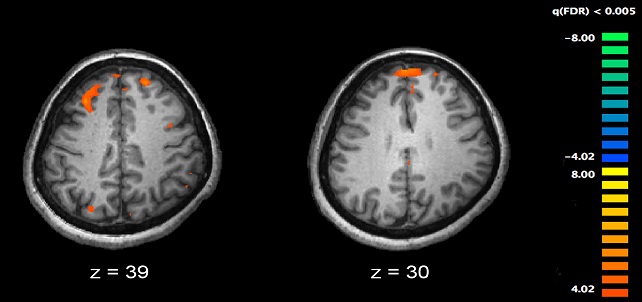

Gut microbes may contribute to the symptoms and brain neurotransmitter changes of schizophrenia. Credit: Julio Licinio and Ma-Li Wong, SUNY Upstate Medical University